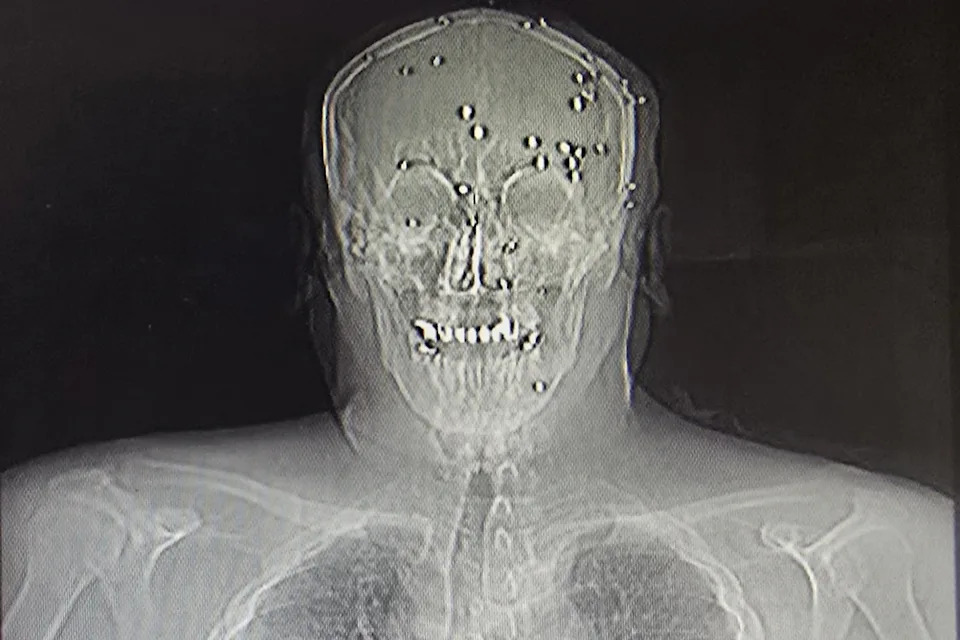

BEIRUT (AP) — As wounded anti-government protesters poured into an Iranian hospital during last month’s crackdown, a young doctor hurried to the emergency room to help treat a man in his 40s who had been shot in the head at close range. When the doctor and others tried to resuscitate the man, a group of armed, plainclothes security agents blocked their way, pushing some back with their rifles, the doctor told The Associated Press. “They surrounded him and didn’t allow us to move further,” the doctor in the northern city of Rasht said. Minutes later, the man was dead. The agents put his body in a black body bag. Later, they piled it and other bodies into the back of a van and drove away. This wasn't an isolated incident. Over the course of a few days in early January, plainclothes agents swarmed hospitals in multiple cities treating the thousands wounded by Iranian security forces who fired on crowds to quash massive protests against the 47-year-old Islamic Republic. These agents monitored and sometimes obstructed care to protesters, intimidated staff, seized protesters and took away the dead in body bags. Dozens of doctors were arrested. This story is based on AP interviews with three doctors in Iran and six Iranian medical professionals living abroad who are in contact with colleagues on the ground; reports from human rights groups; and AP's verification of more than a dozen videos posted on social media. All of the doctors inside Iran spoke on condition of anonymity for fear of retaliation. The AP worked with Mnemonic, a Berlin-based organization, to identify online videos, posts and other material relating to violence in hospitals. The doctors in Iran and abroad said the level of brutality and militarization of health facilities was unprecedented in a country that for decades has experienced crackdowns on dissent and surveillance of public institutions. In at least one instance, snipers on the roof of a hospital in the northern town of Gorgan shot at approaching patients, according to a witness’ account provided by IIPHA, a U.S.-based association of Iranian health care professionals. The Iran Human Rights Center, based in Oslo, has documented multiple accounts from inside hospitals of security agents preventing medical care, removing patients from ventilators, harassing doctors and detaining protesters. “It is systematic," said Amiry-Moghaddam, an Iranian-Norwegian neuroscientist who founded the group. "And we have not experienced this pattern before.” The government has blamed the protests and ensuing violence on armed foreign-backed “terrorists.” Health Ministry spokesman Hossein Kermanpour denied reports of treatment being prevented or protesters being taken from hospitals, calling them “untrue, but also fundamentally impossible.” He was quoted in state media as saying all injured were treated “without any discrimination or interference over political opinions.” The Iranian mission at the United Nations did not immediately reply to a request for comment on the doctors' accounts. The crackdown, which reached its height on Jan. 8 and 9, was the deadliest since the Islamic Republic took power in 1979. A complete toll of casualties and other details have been slow to emerge because of internet restrictions imposed by authorities. The Human Rights Activists News Agency says it confirmed more than 7,000 deaths and that it is investigating thousands more. The government has acknowledged more than 3,000 killed, though it has undercounted or not reported fatalities from past unrest. Once the crackdown began, the doctor in Rasht said he worked through 66 hours of hell, moving each day to a different facility to help with the wounded — first a trauma center, then a hospital and finally a private clinic. On Jan. 8, “every 15 to 30 minutes, the entire emergency ward would be emptied and then refilled with new patients,” the doctor said. It got worse on Jan. 9, as wounds from live ammunition became more common and security agents became more menacing. Agents brought in wounded protesters and stood watch over them as staff worked, the doctor said. They burst into wards, armed with automatic rifles, threatening staff and filming patients and checking documents. When it came time to discharge a patient, he said, “they would take anyone who was confirmed to be a protester.” At one point, security agents brought in the body of a dead man with his hands shackled in front of his body. He had pellet shots to his abdomen and chest and a clear bullet wound to the head, he said. He recognized the man immediately. Only moments earlier, his family had been showing his photo around the hospital, asking if he had been admitted. Amnesty International has received credible reports that targeted, close-range shootings of protesters took place, and “at a far greater scale” than in past crackdowns on protests, said the group’s Iran researcher Raha Bahereini. Two videos verified by AP show the bodies of protesters with close-range shots and medical equipment connected to their bodies. The doctor said he and other staff tried to hide wounded protesters by recording false diagnoses in hospital records. Gunshots to the abdomen were identified as abdominal pain; broken bones were recorded as a falling accident. One patient who had been shot in the genitals was identified as a urology patient. “We knew that no matter what we did for the patients, they wouldn’t be safe once they stepped out of the hospital,” he said. The AP could not independently confirm the doctor’s account of events at the hospital in Rasht. But it conformed with AP’s other reporting. The AP verified videos posted from four hospitals as a snapshot of the Iranian security forces’ activity. Mnemonic gathered dozens of videos, posts and other accounts it says showed forces were present in and around nine hospitals, in some cases firing guns and tear gas. Mnemonic has been preserving digital evidence of human rights violations in Iran since 2022, creating with partners an archive of more than 2 million documents. One video verified by AP shows security agents breaking through glass entrance doors into Imam Khomeini Hospital in the western city of Ilam. They then barged through the halls with their guns, yelling at people. The Health Ministry told state media it was investigating the incident, saying it was committed to protecting medical centers, staff and patients. Other videos verified by AP show a heavy presence of security forces surrounding three hospitals in Tehran, firing tear gas and chasing protesters. Other doctors worked in clandestine centers to treat the wounded away from authorities. On the night of Jan. 8, a 37-year-old general surgeon was out for dinner in Tehran when he received a call from a professional friend he hadn’t heard from in years. The friend, an ophthalmologist, spoke in vague terms, but the fear in her voice made clear she needed his help urgently. She gave him an address. Just before midnight, he drove to the address, a clinic for cosmetic procedures. Inside, he found the lobby transformed into a trauma ward, with more than 30 wounded men, women, children and elderly on the couches and blood-covered floor, shouting and crying, The surgeon spent nearly four days there, treating more than 90 people, he estimates, as volunteers brought in more wounded. At first, it was just him, the ophthalmologist, a dentist and two nurses. He used cardboard boxes and pieces of soft metal as splints for broken bones. With no anesthesia or strong painkillers, he used weaker suppository analgesics. The clinic had no blood supplies or transfusion capabilities, so he administered IV drips to rehydrate them and raise their blood pressure, a process that took hours. At some point that night, phone lines were cut off and for 12 hours, he couldn’t call for more help. They couldn’t send patients to hospitals for fear they’d be arrested. One woman, in her 30s, had been hit by bird shot at close range, destroying the roof of her mouth and the area around her nose and below her eyes, the surgeon recalled. A young man in his 20s had been shot with live ammunition in his elbow, shattering it. The surgeon sutured the wounds but knew the arm would have to be amputated. A family of four — a mother, father and their 8- and 10-year-old children — were all riddled with pellets, the surgeon said. The older boy had dozens of pellets in his face, but amazingly none hit his eyes. On the morning of Jan. 9, the phone lines started working again, and the surgeon reached out to doctors he trusted to refer patients to them. First he had to make sure to remove all bullets and pellets from their bodies so they wouldn’t be detained at the hospital. He wrote referral letters saying the patients had been in car accidents. The surgeon summoned three other doctors to help in the hidden clinic. When new wounded were brought in, the patients who had been stabilized applauded and flashed victory signs to them, he said. “They started to make the atmosphere happy through their pain. … I just couldn’t believe that moment,” the surgeon said, his voice breaking. “It was so human.” None of the wounded died at the clinic, though two dead bodies with gunshot wounds to the head were brought in, he said. The AP could not independently confirm the surgeon's account of events at the clinic. Since Jan. 9, at least 79 health care professionals have been detained, including a dozen medical students, according to Homa Fathi, an Iranian dentist pursuing a Ph.D. in Canada and member of IIPHA who has been monitoring Iranian government action against health professionals since 2022. Many of those detained were accused of resisting security agents’ orders or other charges connected to providing medical care to protesters, said Fathi. Around 30 have been released, most on bail, but many of them still face charges, including one accused of “waging war against God,” a charge that carries a death penalty, Fathi said. Authorities are also keeping some doctors under surveillance at home to ensure they don’t receive or visit wounded protesters — an unprecedented level of control, she said. The surgeon who treated protesters at the secret clinic said he was surprised security forces never stormed that location to make arrests. But arrests have come since. Two health care workers who volunteered at the clinic were seized from their homes, the surgeon said. “I am waiting, too.”